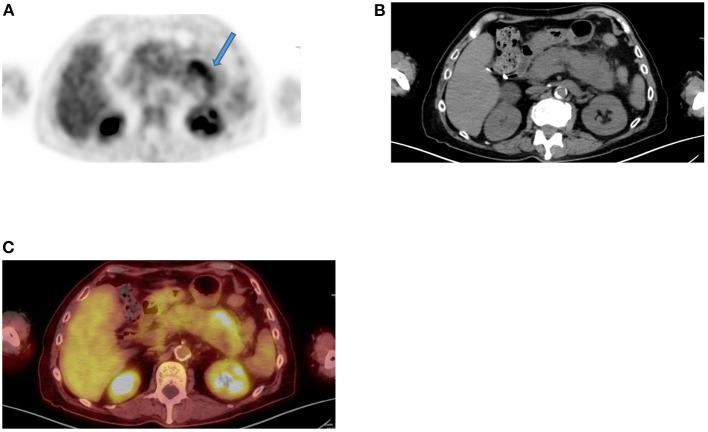

Since its introduction into clinical practice, multimodality imaging has revolutionized diagnostic imaging for both oncologic and non-oncologic pathologies. F-fluorodeoxyglucose (F-FDG) PET/CT imaging which takes advantage of increased anaerobic glycolysis that occurs in tumor cells (Warburg effect) has gained significant clinical relevance in the management of most, if not all oncologic conditions. Because FDG is taken by both normal and abnormal tissues, PET/CT imaging may demonstrate several normal variants and imaging pitfalls. These may ultimately impact disease detection and diagnostic accuracy. Imaging specialists (nuclear medicine physicians and radiologists) must demonstrate a thorough understanding of normal and physiologic variants in the distribution of F-FDG; including potential imaging pitfalls and technical artifacts to minimize misinterpretation of images. The normal physiologic course of F-FDG results in a variable degree of uptake in the stomach, liver, spleen, small and large bowel. Urinary excretion results in renal, ureteric, and urinary bladder uptake. Technical artifacts can occur due to motion, truncation as well as the effects of contrast agents and metallic hardware. Using pictorial illustrations, this paper aims to describe the variants of physiologic F-FDG uptake that may mimic pathology as well as potential benign conditions that may result in misinterpretation of PET/CT images in common oncologic conditions of the abdomen and pelvis.

自从多模态成像技术引入临床实践以来,它已经彻底改变了肿瘤和非肿瘤疾病的诊断成像。利用肿瘤细胞中发生的无氧糖酵解增加(瓦伯格效应)的F-氟脱氧葡萄糖(F-FDG)PET/CT成像,在大多数(即使不是全部)肿瘤疾病的管理中已具有重要的临床意义。由于正常组织和异常组织都会摄取FDG,PET/CT成像可能会显示出几种正常变异和成像陷阱。这些最终可能会影响疾病检测和诊断准确性。成像专家(核医学医师和放射科医生)必须充分了解F-FDG分布中的正常和生理变异;包括潜在的成像陷阱和技术伪影,以尽量减少对图像的错误解读。F-FDG的正常生理过程会导致胃、肝脏、脾脏、小肠和大肠出现不同程度的摄取。尿液排泄会导致肾脏、输尿管和膀胱摄取。由于运动、截断以及造影剂和金属硬件的影响,可能会出现技术伪影。本文旨在通过图片说明,描述可能模仿病变的生理性F-FDG摄取变异,以及在腹部和骨盆常见肿瘤疾病中可能导致PET/CT图像误判的潜在良性情况。